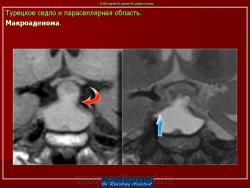

Патология области турецкого седла.

впервые настолько глубокие изменеия турецкого седла, что даже не требуется дообследование.